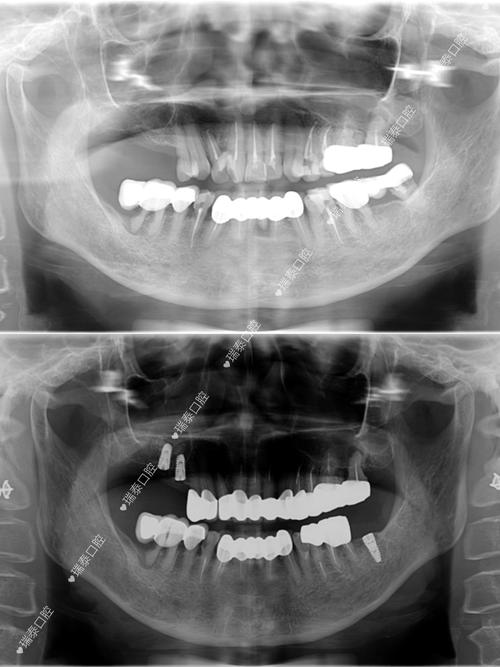

- 精准影像诊断: 普遍配备高分辨率CBCT(锥形束CT)、全景片、口内扫描仪等,能精确评估牙槽骨量、密度、神经血管位置,制定精准的种植方案。

- 数字化诊疗: 很多医院已引入数字化种植导板技术,实现手术的精准化和微创化。